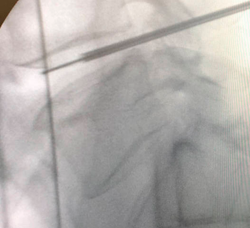

TÉCNICAS UNIDAD DEL DOLOR

En los casos en los que no se controle el dolor con el tratamiento conservador el siguiente paso es realizar una infiltración foraminal o una infiltración epidural, lo que hacemos es introducir una aguja bien en el espacio que rodea el saco dural o en el agujero por el que sale la raíz nerviosa para depositar en este lugar una medicación antiinflamatoria (normalmente un corticoide y anestésico local) que difunde por los tejidos y reduce el dolor.

En caso de dolor más localizado y que afecte a una raíz en concreto, se podría realizar una radiofrecuencia pulsada, esta técnica consiste en introducir un catéter cerca de la raíz nerviosa que emite radiofrecuencia (calor), que va a alterar la transmisión del dolor, disminuyendo la intensidad de la señal dolorosa que va a recibir el cerebro. También va a disminuir el umbral doloroso, es decir se necesitará un estímulo doloroso más potente para sentir dolor. Se trata de una técnica que se realiza con anestesia local y sedación y es ambulatoria.